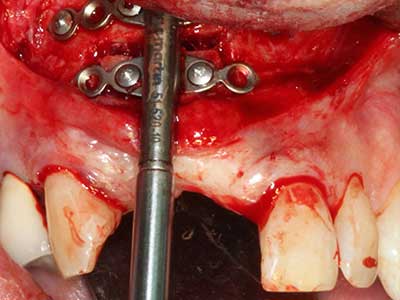

Fig. 27: 21-year-old patient after conversion osteotomy with persistent retrognathy with class II dysgnathy.

Fig. 28: During removal of metal, the basal chin regions are separated with the Piezomed while retaining the lingual blood supply.

Fig. 29: Forward displacement of the chin by 5 mm and fixation with two osteosynthesis plates (KLS Martin). The two mental nerves can be detected in the marginal region.

Fig. 30: The aesthetic improvement in the chin contour after the operation can be clearly seen.